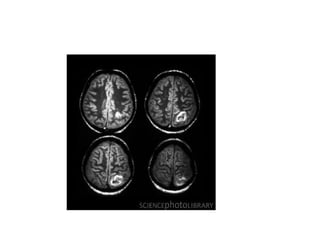

Lacunar infarcts

• Lacunar infarcts are small infarcts in the deeper parts of

the brain (basal ganglia, thalamus, white matter) and in

the brain stem.

• Lacunar infarcts are caused by occlusion of a single

deep penetrating artery.

• Lacunar infarcts account for 25% of all ischemic strokes.

• Atherosclerosis is the most common cause of lacunar

infarcts followed by emboli.

MR Findings

• Tl WI: Small, well circumscribed hypointense foci

• T2WI: Small, well circumscribed hyperintense foci

• FLAIR:Typically increased in signal

• DWI

o Restricted diffusion (hyperintense) if acute/subacute

o May show small lesions otherwise undetectable

• Tl C+: May enhance if late acute/early subacute

• MRA: Normal